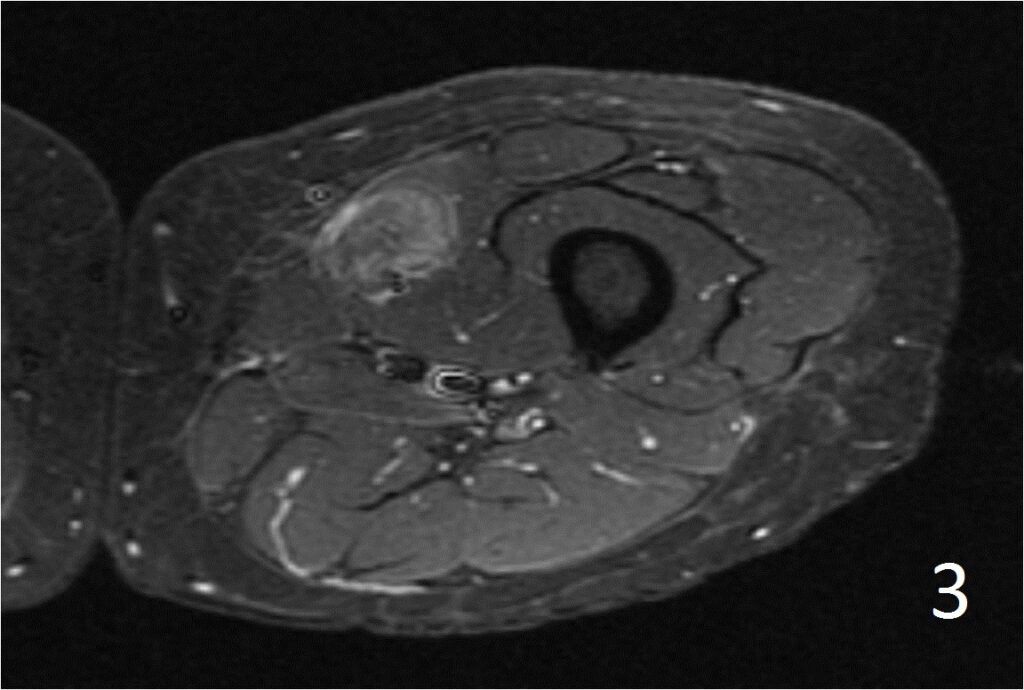

MRI

• Well defined heterogeneous mass on T1W and IR sequences (Fig. 2, 3) heterogeneous enhancement on postcontrast images (Fig. 4)

Fig. 2-4: Axial T1W FS of the thigh shows a ill-defined mass in medial thigh, and fairly well defined and heterogeneous on IR sequence (Fig. 3). Axial T1W displays a heterogeneous mass with mild enhancement post gadolinium (Fig. 4)